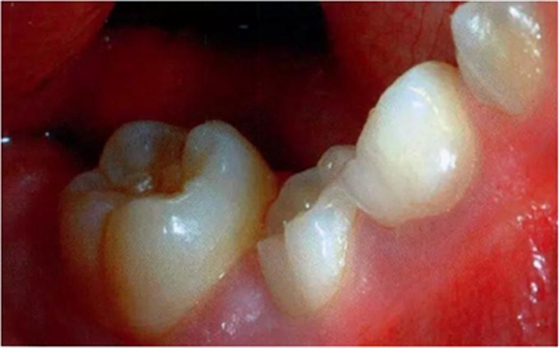

圖3:重度下沉的臨床像